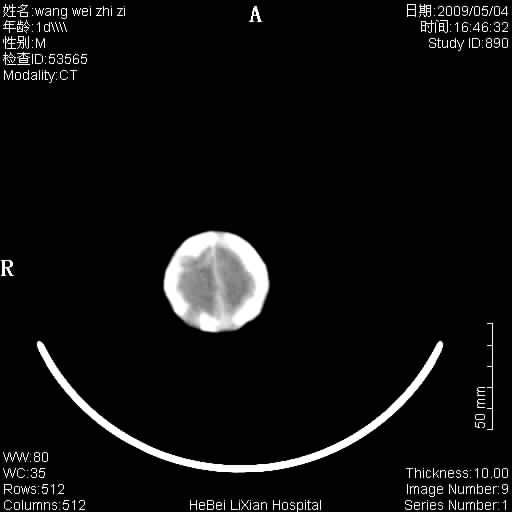

患者,男,1天,上肢抽动数次伴气促.有急产史.可以诊断珠网膜下腔出血吗?

缺血缺氧性脑病,蛛网膜下腔出血。

此例符合缺血缺氧性脑病并蛛网膜下腔出血.